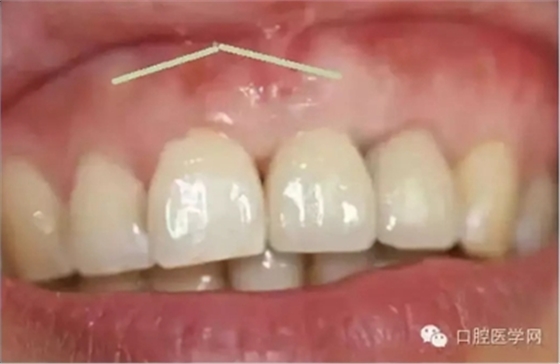

在臨床上我們需要把牙槽骨增生和骨隆突區(qū)分開來,骨隆突是在頜骨上的生理性骨性突起,并不是一個(gè)疾病癥狀,也不是疾病的表現(xiàn),比如舌側(cè)骨隆突、上頜骨骨隆突、下頜隆突是在第三磨牙和雙尖牙舌側(cè)的一個(gè)生理性突起。